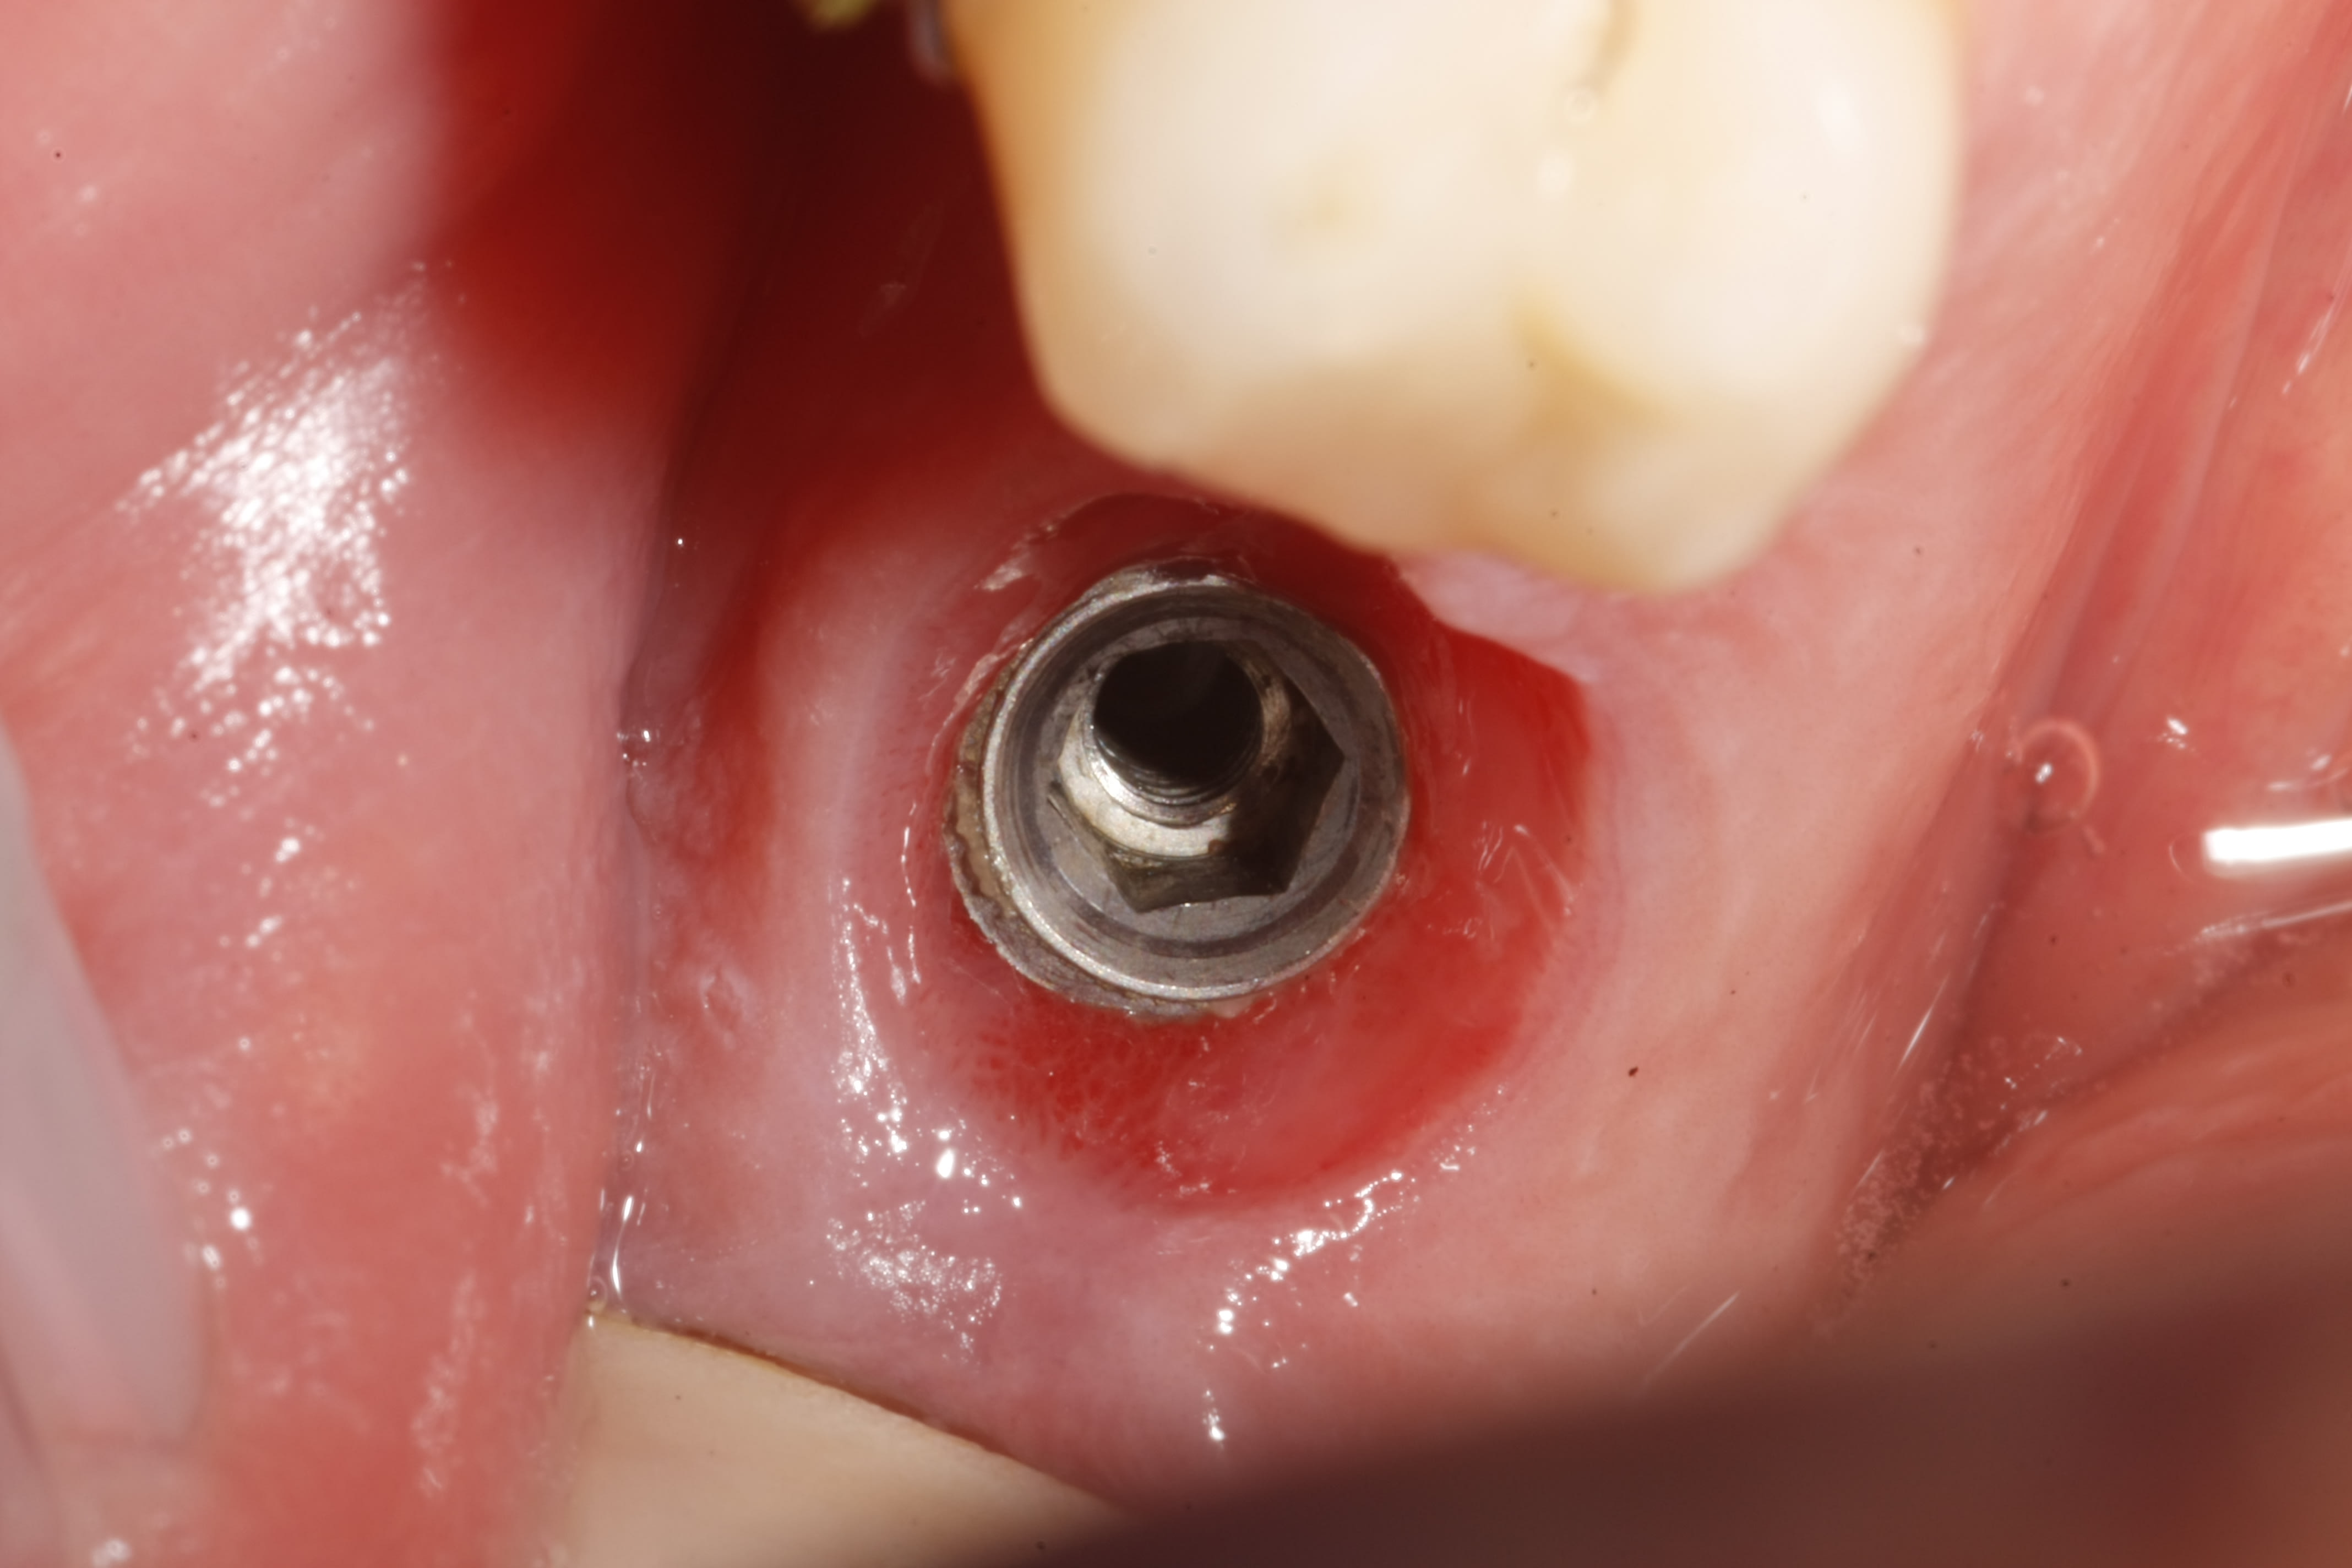

J'aurai besoin d'un ptit coup de main des experts pour identifier la bête.

Au début, je pensais à un NobelActive, surtout que le tournevis étoile avait bien marché pour dévisser le pilier, mais à l'essayage du transfert RP, ça ne colle pas. Et l'hexagone fait 2,40mm de méplat à méplat, donc pas Nobel RP...

Est-ce que ce serait un Narrow Platform ?

Je suis retourné dans WhatImplantIsThat, et je me demande si je n'ai pas confondu avec un AlphaBio SPI ou un ADIN Touareg (implants que je ne connais pas du tout...)